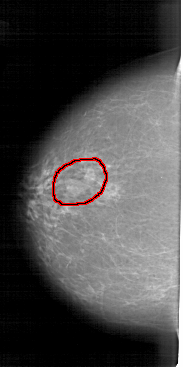

A_1942_1.RIGHT_CC

FILE: A_1942_1.LEFT_CC.OVERLAY

TOTAL_ABNORMALITIES 1

ABNORMALITY 1

LESION_TYPE MASS SHAPE LOBULATED MARGINS ILL_DEFINED

ASSESSMENT 4

SUBTLETY 5

PATHOLOGY BENIGN

TOTAL_OUTLINES 1

BOUNDARY

LEFT_CC LINES 5131 PIXELS_PER_LINE 2551 BITS_PER_PIXEL 12 RESOLUTION 43.5 OVERLAY